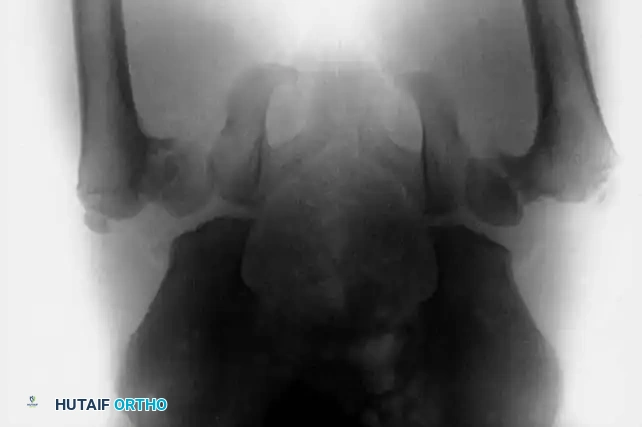

Clinical and Radiographic Evaluation

Early diagnosis is critical, as the likelihood of achieving a functionally normal hip diminishes precipitously after 8 years of age. Radiographic evaluation must include weight-bearing anteroposterior (AP) and frog-leg lateral views of the pelvis.

Key radiographic parameters include the neck-shaft angle and the Hilgenreiner epiphyseal angle (HEA). The HEA is the angle subtended by a horizontal line drawn through the triradiate cartilages (Hilgenreiner's line) and a line drawn parallel to the proximal femoral physis. A normal HEA is less than 25 degrees; an angle greater than 60 degrees is an absolute indication for surgical intervention due to the 100% rate of progression.